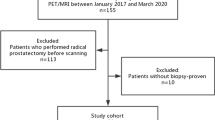

At Essen University Hospital, patients with advanced prostate cancer who show disease progression despite chemotherapy are considered for [177Lu]Lu-PSMA-617 therapy. Assessment for this treatment includes a pre-therapy PSMA-PET/CT examination with increased uptake of PSMA ligands and verification of good renal and bone marrow function. These patients have high tumor burden and are followed up over an extended period at our site, thus providing valid clinical data for the survival analysis. In total, 78 patients were retrospectively included in this study. Patients with advanced prostate cancer who received [177Lu]Lu-PSMA-617 radioligand therapy (RLT) from January 2018 to December 2020 were initially identified in the local database. The inclusion criteria were histopathologically proven adenocarcinoma of the prostate and the presence of an on-site [68Ga]Ga-PSMA-11 PET/CT examination before administration of the first cycle of [177Lu]Lu-PSMA-617 radionuclide therapy. PSA values were obtained within 30 days of the diagnostic PET/CT examination in an outpatient setting and before the first [177Lu]Lu-PSMA617 radionuclide therapy. At the time of PET/CT imaging, all patients had advanced prostate cancer (UICC stage IV). Overall survival (OS) was defined as the time from the first cycle of RLT until death or last follow-up. Detailed patient characteristics are listed in Table 1. The study was approved by the institutional review board and local ethics committee (Ethics committee, University Duisburg-Essen, Faculty of Medicine, Ethics protocol number 19-8570-BO). The patients gave written informed consent for the clinical examination.